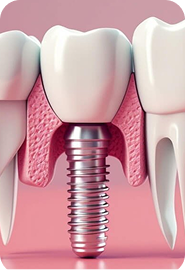

Endosteal Implants

Endosteal implants are inserted into the jawbone through a minor surgical procedure, and are the most commonly used dental implant. They are usually made from titanium or zirconia materials.

Implants Surgically Inserted into the Jawbone

Your implants will be inserted into your jawbone by a minor surgical procedure. We will use local anesthesia so you will feel no pain during this procedure.

Osseointegration

After the dental implants have been inserted, the process of osseointegration begins. This process will take several months, allowing the implants to bond and integrate with the jawbone.

Placement of the Abutment

Once the implant has fully fused with the jawbone, the abutment is placed. This will support the prosthetic tooth and hold it in place on the implant.